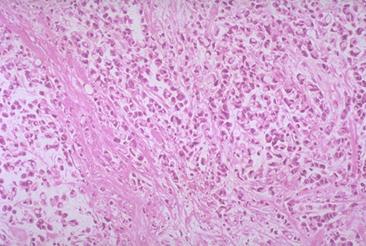

clasificación del pacienteTumor Epitelial Maligno/Cáncer a células en Sello de Anillo

parte(separada por órganos)colon/recto

método de exámenMicro

clasificación ectoscópica de tumoresTipo 3(Tipo ulcerado de bordes infiltrados)/

diámetro mayor del tumor35 - 40

grado de penetracións(a)